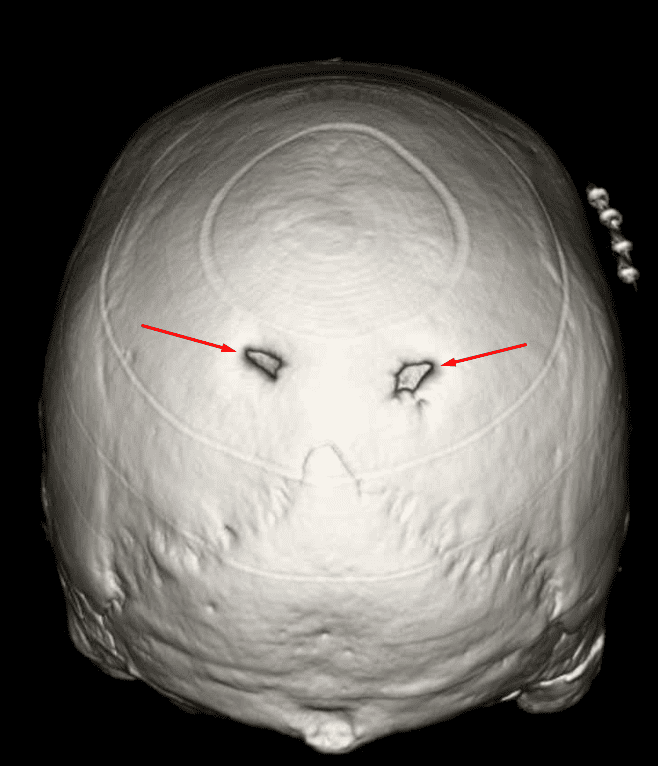

Enlarged Parietal Foramina

Case 12